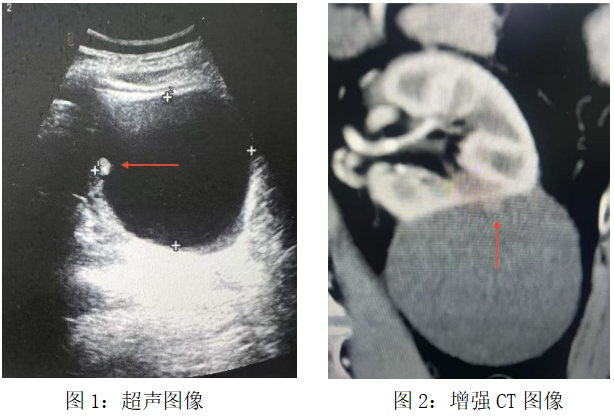

它看起来只是一个普通的肾脏囊肿——8厘米大小,表面光滑,在灰阶超声图像上安静得像个无害的“水泡”。

直到超声医生的探头停留在某个细微处:囊肿内壁上,一个仅7毫米大小的实性结节,如同沉睡的火山,暗示着平静表面下的汹涌。这是一位老年男性的体检报告,却成了北京大学首钢医院泌尿肿瘤MDT团队接到的“集结令”。

“这个囊肿不单纯,警惕恶性肿瘤风险,需要做个增强 CT 确认一下。”超声科医生的判断拉响了第一声警铃。常规体检报告上的“肾囊肿”本是临床上常见良性病症,可这枚比指甲盖还小的结节,却像一个持续闪烁的红色警报,在超声医生心里不断回响。

增强CT的结果证实了担忧:Bosniak Ⅳ级复杂肾囊肿,恶性概率极大。所谓复杂肾囊肿是指囊肿存在囊壁增厚、分隔、钙化、实性结节等情况,如同裹着糖衣的“定时炸弹”,必须尽快启动专科诊疗。